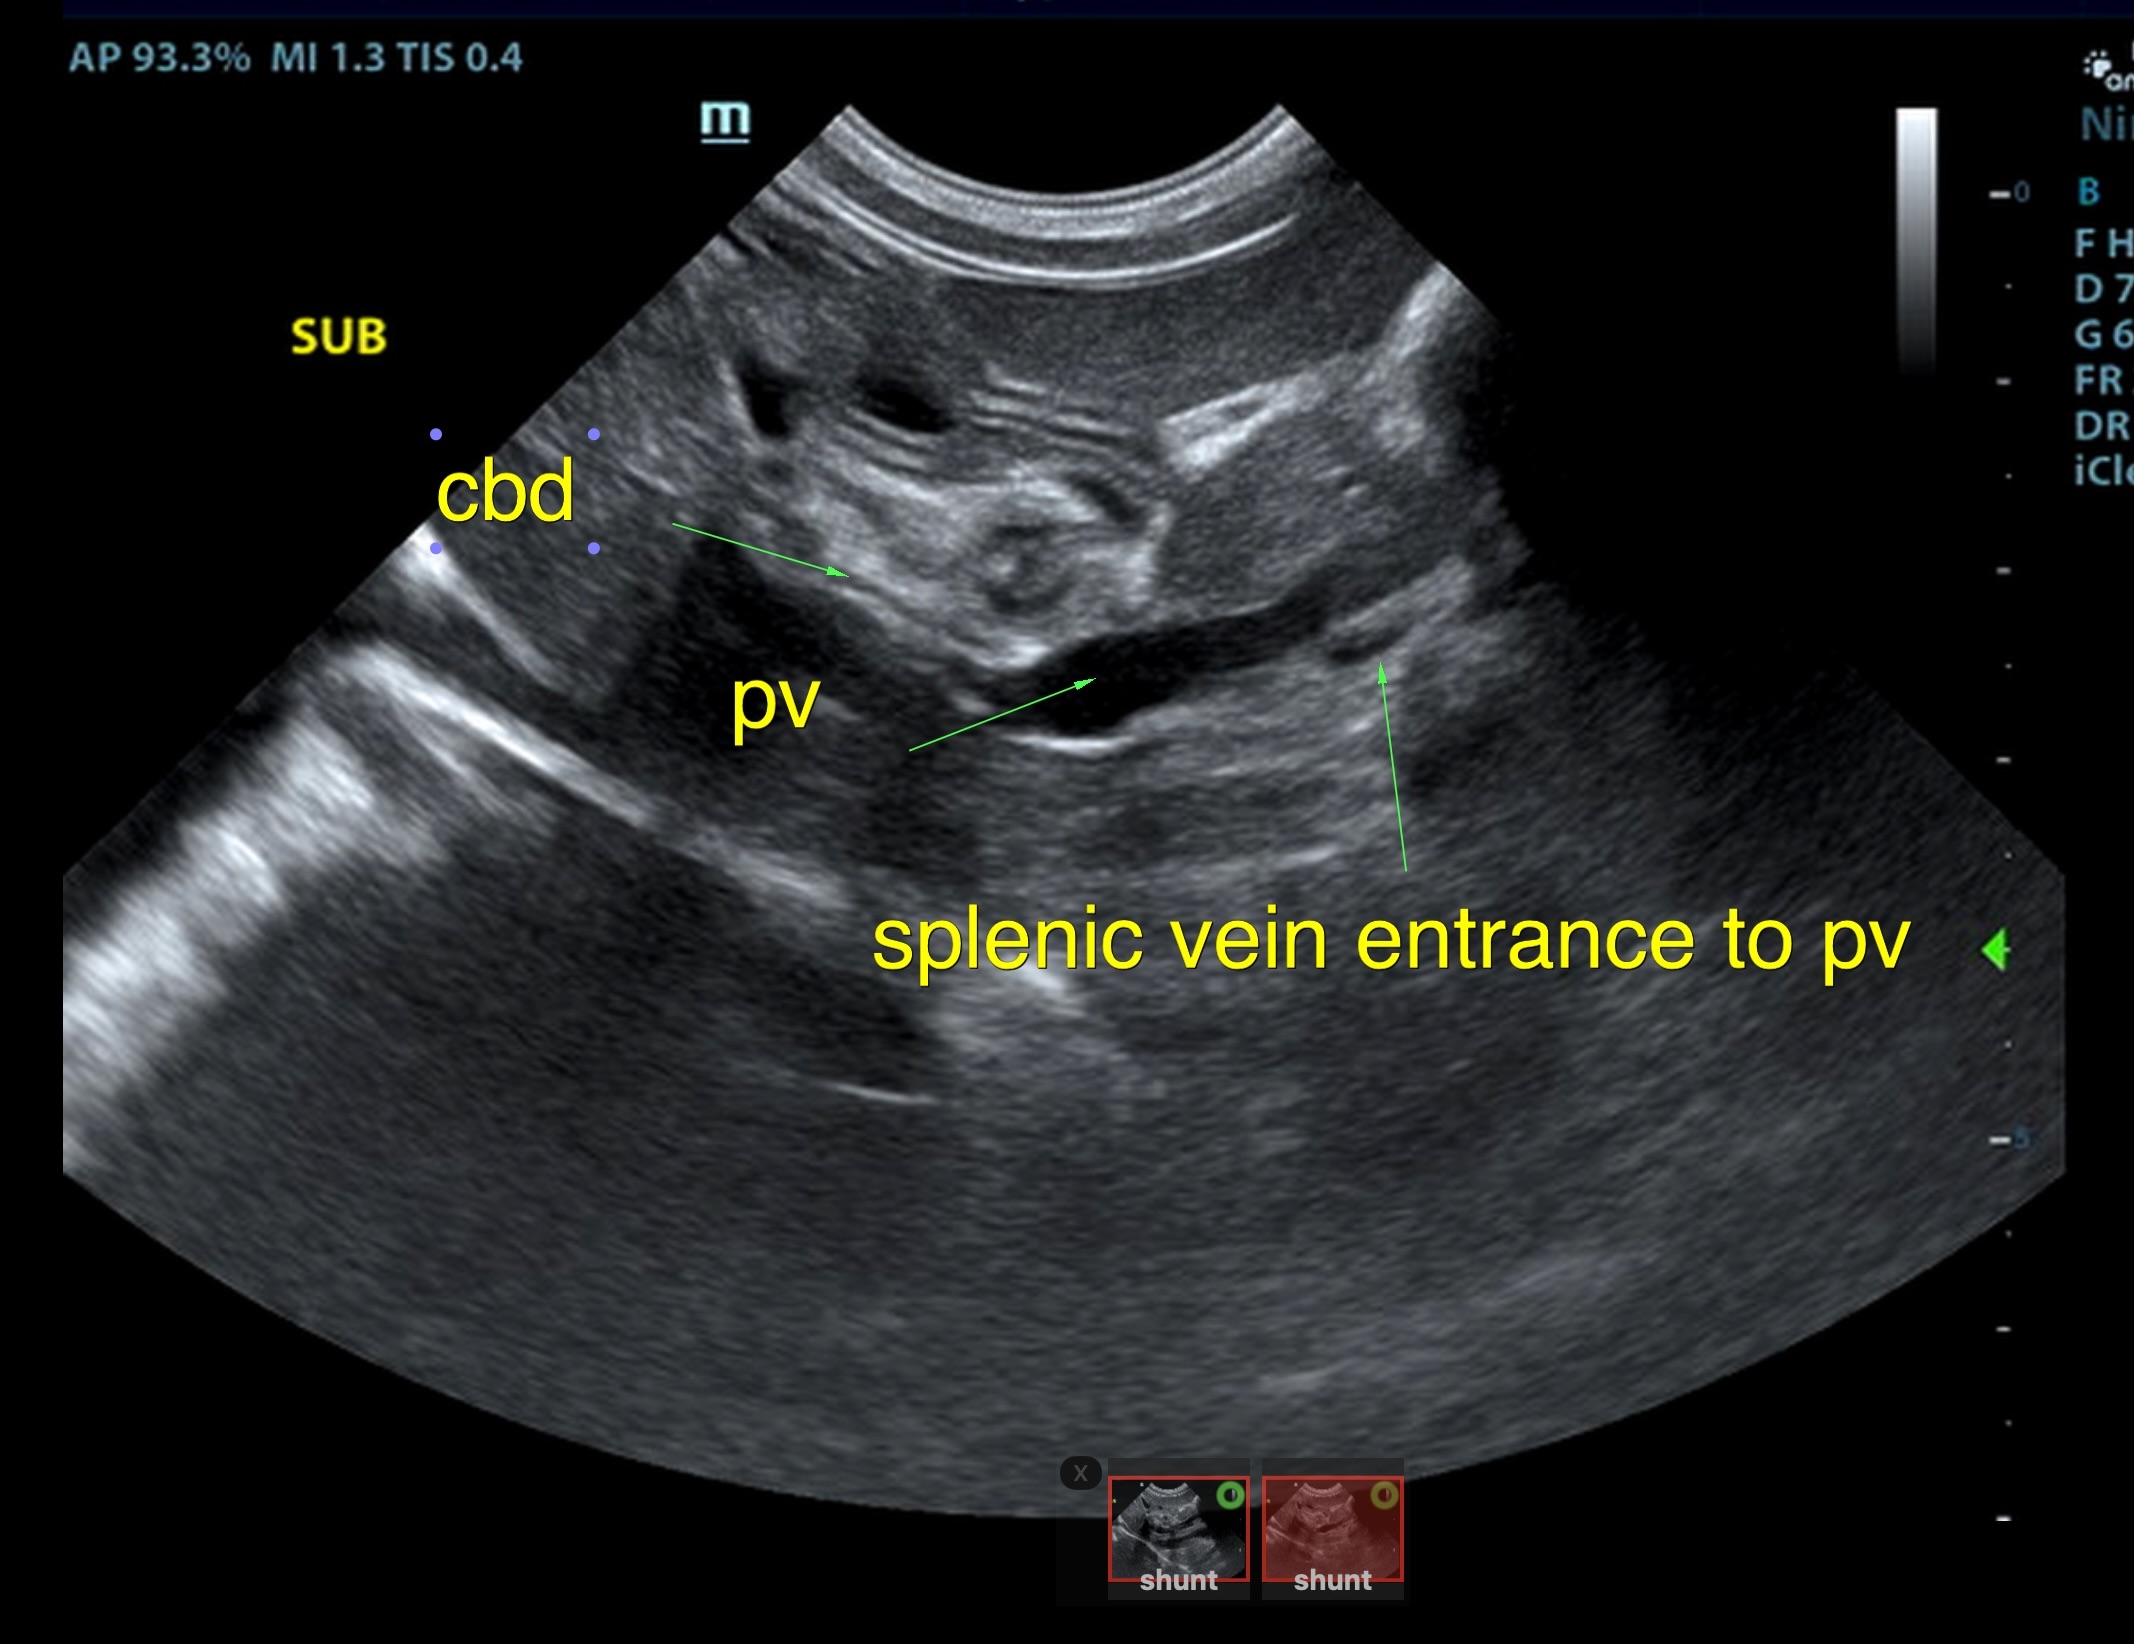

The liver was subnormal in size, yet the portal vein and vena cava ratio was 1:1. The portal veins were subnormal in size and measured 0.34 cm. The vena cava was enlarged and measured 0.34 cm. The vena cava was enlarged and measured 0.72 cm, aorta measured 0.4 cm. The branching of the portal vein appeared to be normal and of adequate volume. The portal vein and vena cava measured 0.5 cm each in the extrahepatic space. The splenic vein entry into the portal vein and gastroduodenal vein entry into the portal vein appear to be normal. There was one turbulent vessel in the region of the central branch of the portal vein, which may represent an intrahepatic shunt, but this could not be confirmed. The width of the shunt is approximately 0.76 cm. This is in position of central divisional shunt; however, right divisional origin cannot be completely ruled out. The gallbladder presented acceptably thin walls with primarily anechoic content. The cystic and common bile ducts were normal.